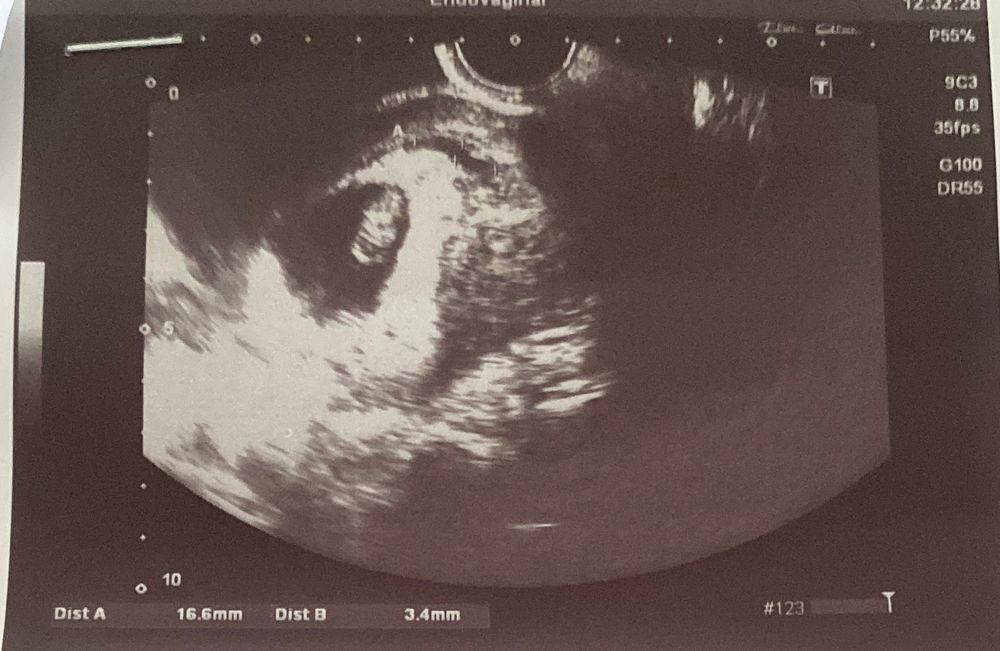

ровно две недели назад была 7мм, сейчас 16мм, были сильные стрессы. Как долго вы лечили эту проблему и реально ли прогестерон помогает?

современные врачи уже считают иначе, меня по какой-то причине не положили в стационар, хотя гематома достаточно большая? Врач ничего не сказал, подскажите, гематома в месте где ребеночку опасно или нет? Срок 9недель